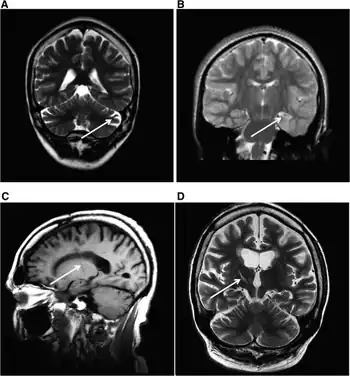

MRI (adult) showing cerebellar atrophy in Dravet syndrome | |

The cause if often a genetic mutation in the SCN1A gene.[4] Around 90% of mutations newly occur during early development, rather then being inherited from a person's parents.[3] A family history of seizures is present in nearly half of cases.[8] Diagnosis is based on symptoms and genetic testing.[5] MRI of the brain is typically normal initially, though may show changes such as atrophy in some adults.[2]